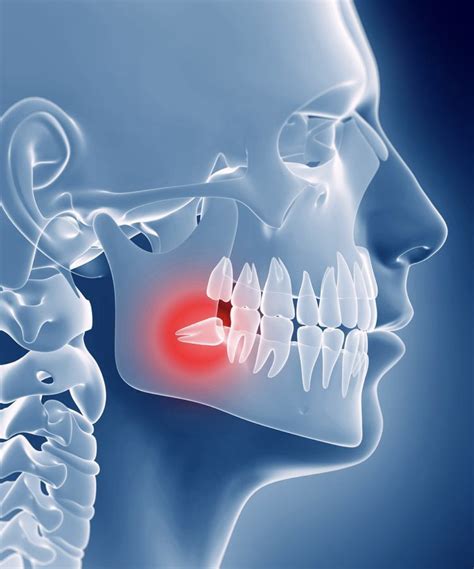

- Mala posición: su posición inclinada o torcida en la boca puede provocar que queden atrapadas y no puedan salir del todo, lo que puede provocar inflamación, malestar al comer y dolor al hacer presión sobre los otros dientes.

- Quistes: cuando una muela del juicio no logra erupcionar (cordales incluidos) y están totalmente cubiertas por la encía, se asocia a la formación de quistes.